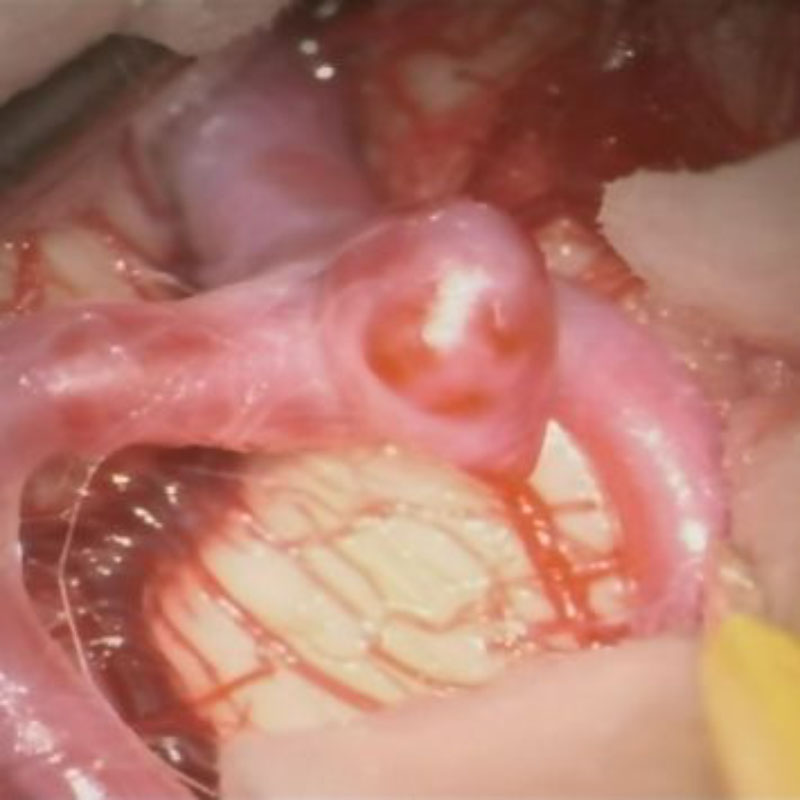

手術前

クリップ前

クリップ後

手術後